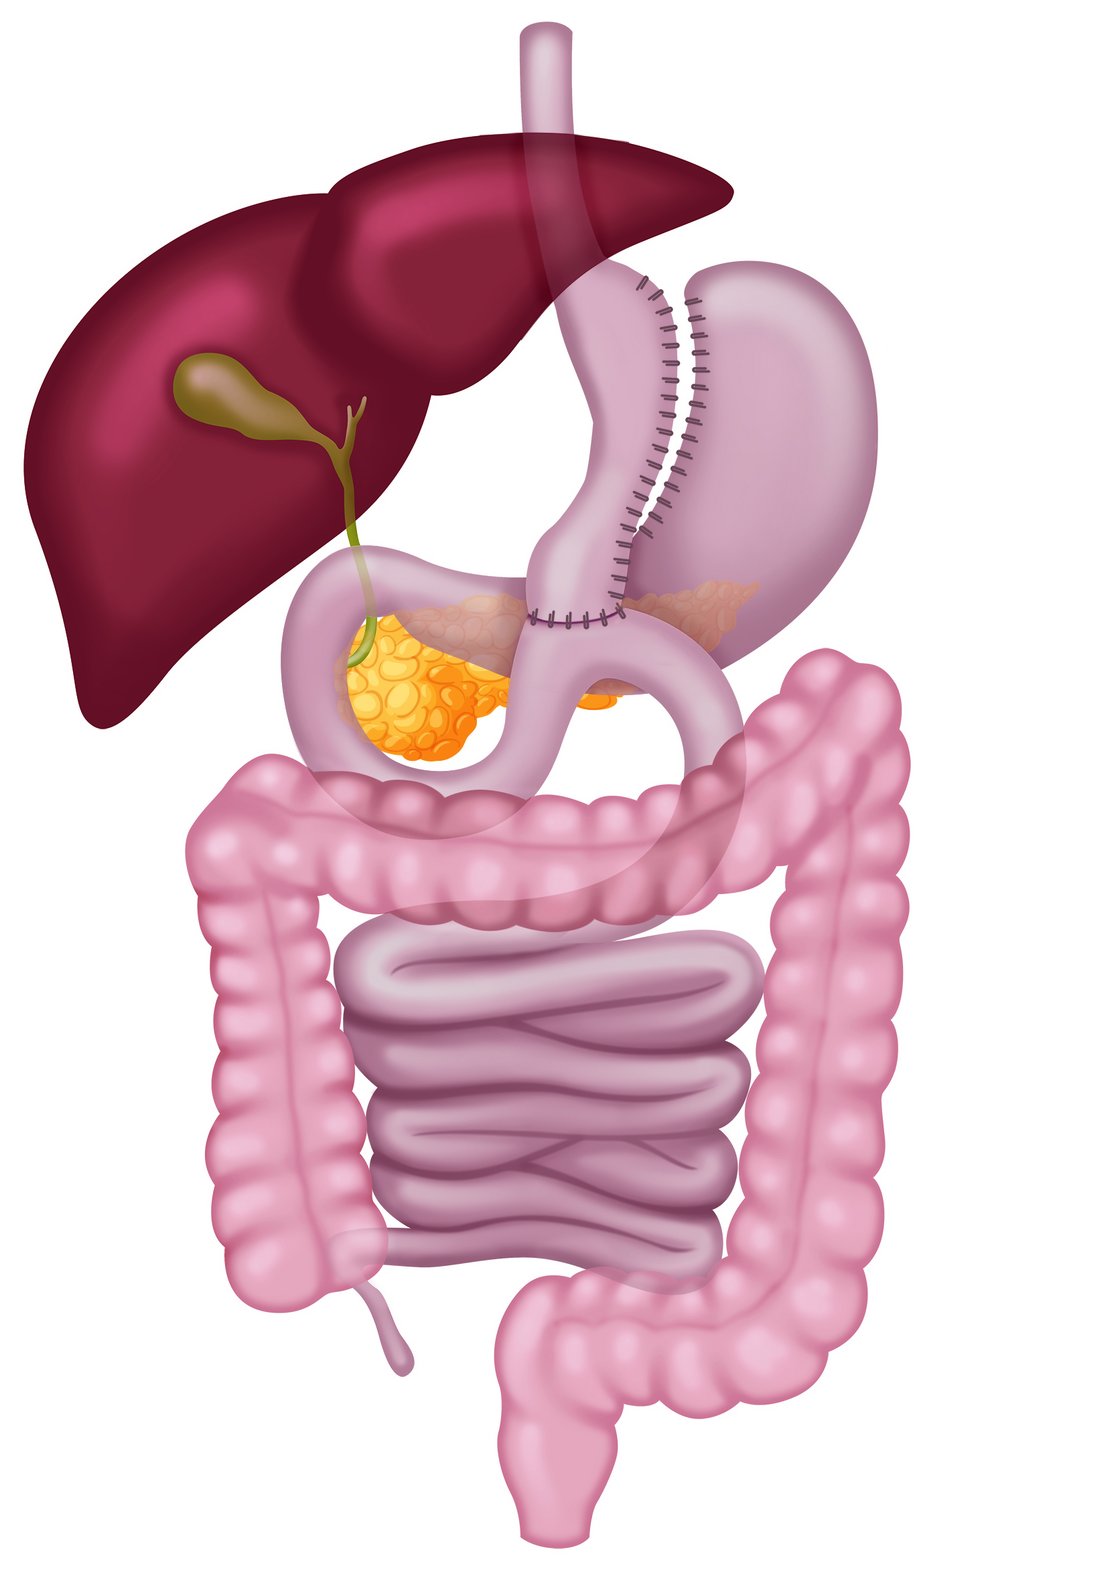

- bei Reflux

- BMI 45-60 kg/m², zusätzlich Diabetes

- Verkleinerung des Magens (Magenpouch) und Umstellung der Nahrungspassage mit einer Nahtverbindung (Anastomose)

- zusätzliche Aufnahme von Vitaminen und Spurenelementen notwendig